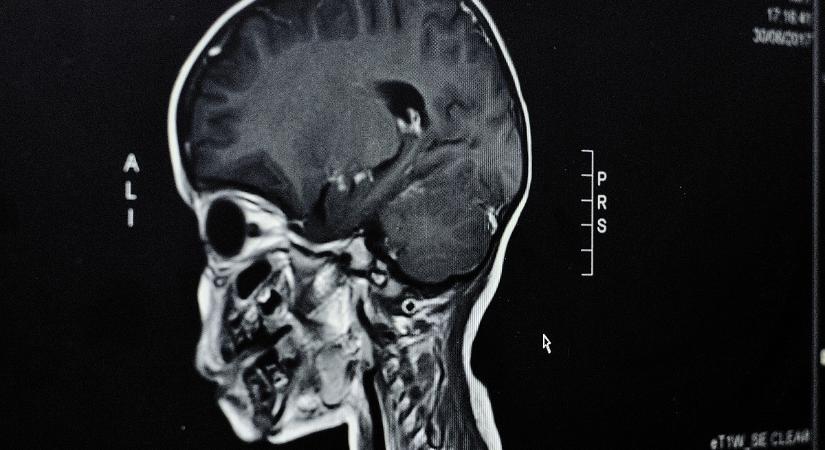

Brit kutatók arra figyelmeztetnek, hogy a központi idegrendszer befolyásolására képes neurofegyverek egyre növekvő biztonsági fenyegetést jelentenek. A technológia fejlődése miatt ezek ... ...